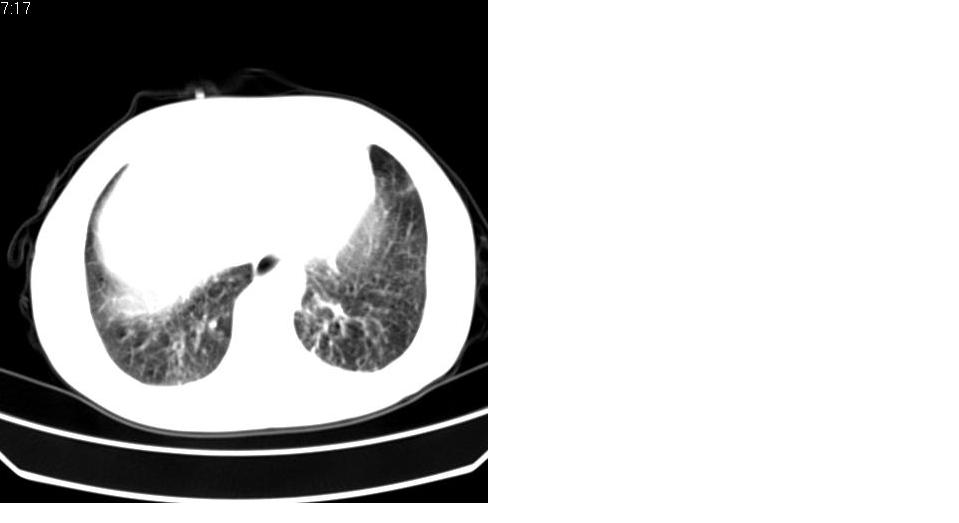

标题: CT16839:胸部CT平扫

女 50岁,在其他医院确诊肺癌.

支持 右肺上叶肺癌并两肺及纵隔转移。

先考虑:肺癌伴肺转移。

建议:结合临床资料,或穿刺活检,除外继发性肺结核之可能。